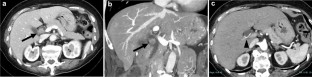

Recently, the number of reports describing patients with initially unresectable biliary tract cancer (BTC) who underwent resection in the form of conversion surgery is increasing. Gemcitabine plus cisplatin (GC) combination therapy has been reported to significantly prolong the median survival time from 8.1 to 11.7 months compared with conventional gemcitabine therapy in patients with unresectable BTC. We report the case of a patient with unresectable BTC who underwent conversion surgery with a partial response to GC combination therapy. A 78-year-old woman was diagnosed with unresectable BTC with invasion of the right hepatic artery by lymph node metastasis and liver metastases. The patient received GC combination therapy. After 6 cycles of chemotherapy, the patient achieved a partial response. The radiological findings revealed a marked shrinkage in the primary lesion and the disappearance of lymph node and liver metastases. Therefore, the patient underwent conversion surgery, including biliary tract resection and regional lymph node dissection. For postoperative follow-up, the patient was monitored without receiving adjuvant chemotherapy. The patient had not exhibited recurrence during the 12-month follow-up period. We report the case of a patient with unresectable BTC who underwent conversion surgery with a partial response to GC combination therapy.